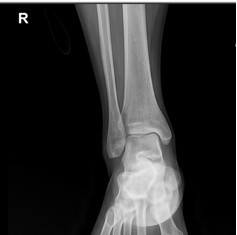

이러한 발목의 방사선 촬영을 해보면 하퇴골, 비골 그리고 거골이 만나는 관절면의 거리가 일정하지 않고, 일부는 좁고 일부는 넓어진 비대칭성을 보입니다. 이러한 소견은 발목의 인대의 파열을 의심하게 하는 방사선 소견입니다.

위에서 말씀드린 31세의 여성분의 방사선 소견에서도 이러한 관절면의 비대칭성이 보였습니다.